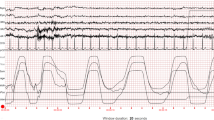

ABSTRACT. We studied the activity of the diaphragm and of the genioglossus at the onset and at the end of obstructive sleep apnea in children. Seven children (mean age 46 months, range 15–87) with obstructive sleep apneas mainly due to enlarged tonsils were tested during natural sleep. We recorded sleep stages (neurophysiological criteria), nasal and buccal air flow (thermistors), thoracoabdominal motion (magnetometers), genioglossus and diaphragm electromyographic activity (EMG) (surface electrodes), and transcutaneous partial pressure of oxygen (Radiometer 44° C). A total of 153 obstructive apneas for the whole group of patients was studied. Compared to the preceding unoccluded breaths, genioglossus and diaphragm EMG data showed that 1) at the onset of obstructive apnea there was no significant decrease in genioglossus and/or diaphragm EMG, contrasting with published data for obese adults, and 2) at the end of obstructive apnea, significant preferential increase in genioglossus EMG, not related to the decrease in transcutaneous partial pressure of oxygen, was found as in obese adults. This study showed that different mechanisms may control the onset of obstructive apnea in children as compared to adults, whereas children and obese adults share the same preferential increase in genioglossus EMG at the end of obstructive apnea.